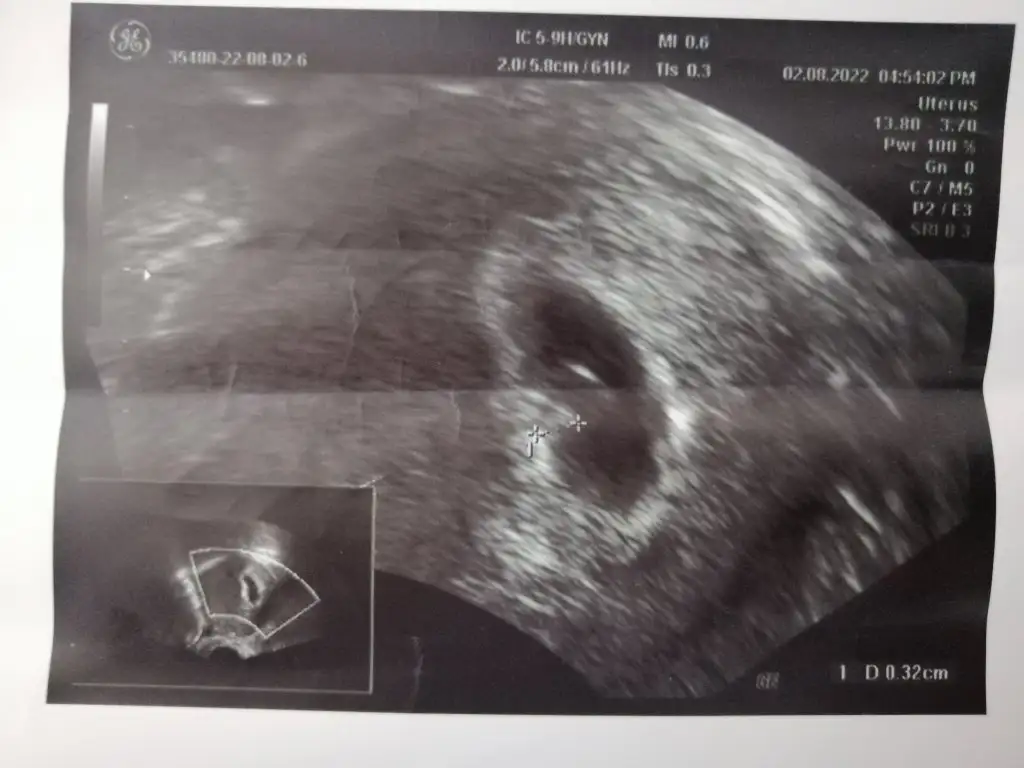

Henüz 4 haftalık ama şansımı deneyim dedim dedim alttan muayene ile bakıldı🤗

• IMG-20221006-WA0019.webp

IMG-20221006-WA0019.webp

20 KB · Görüntüleme: 75